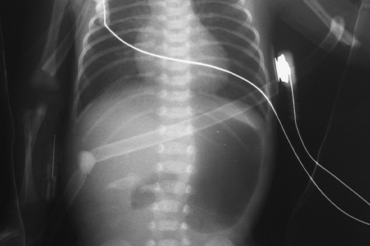

Atresia de Esofago

Neonatal y Lactante